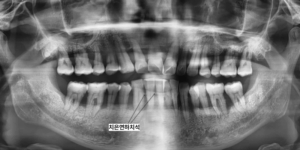

초진 내원 당시 환자분의 구강 내에는

28개의 모든 치아에서 치조골 파괴가

심하게 진행되어 있었고

치은연하치석이 거의 전 영역에

걸쳐 침착된 상태였습니다.

x-ray상에서 잇몸아래쪽 치아 옆에 뾰족하게

붙어있는 것들이 치은연하치석입니다.